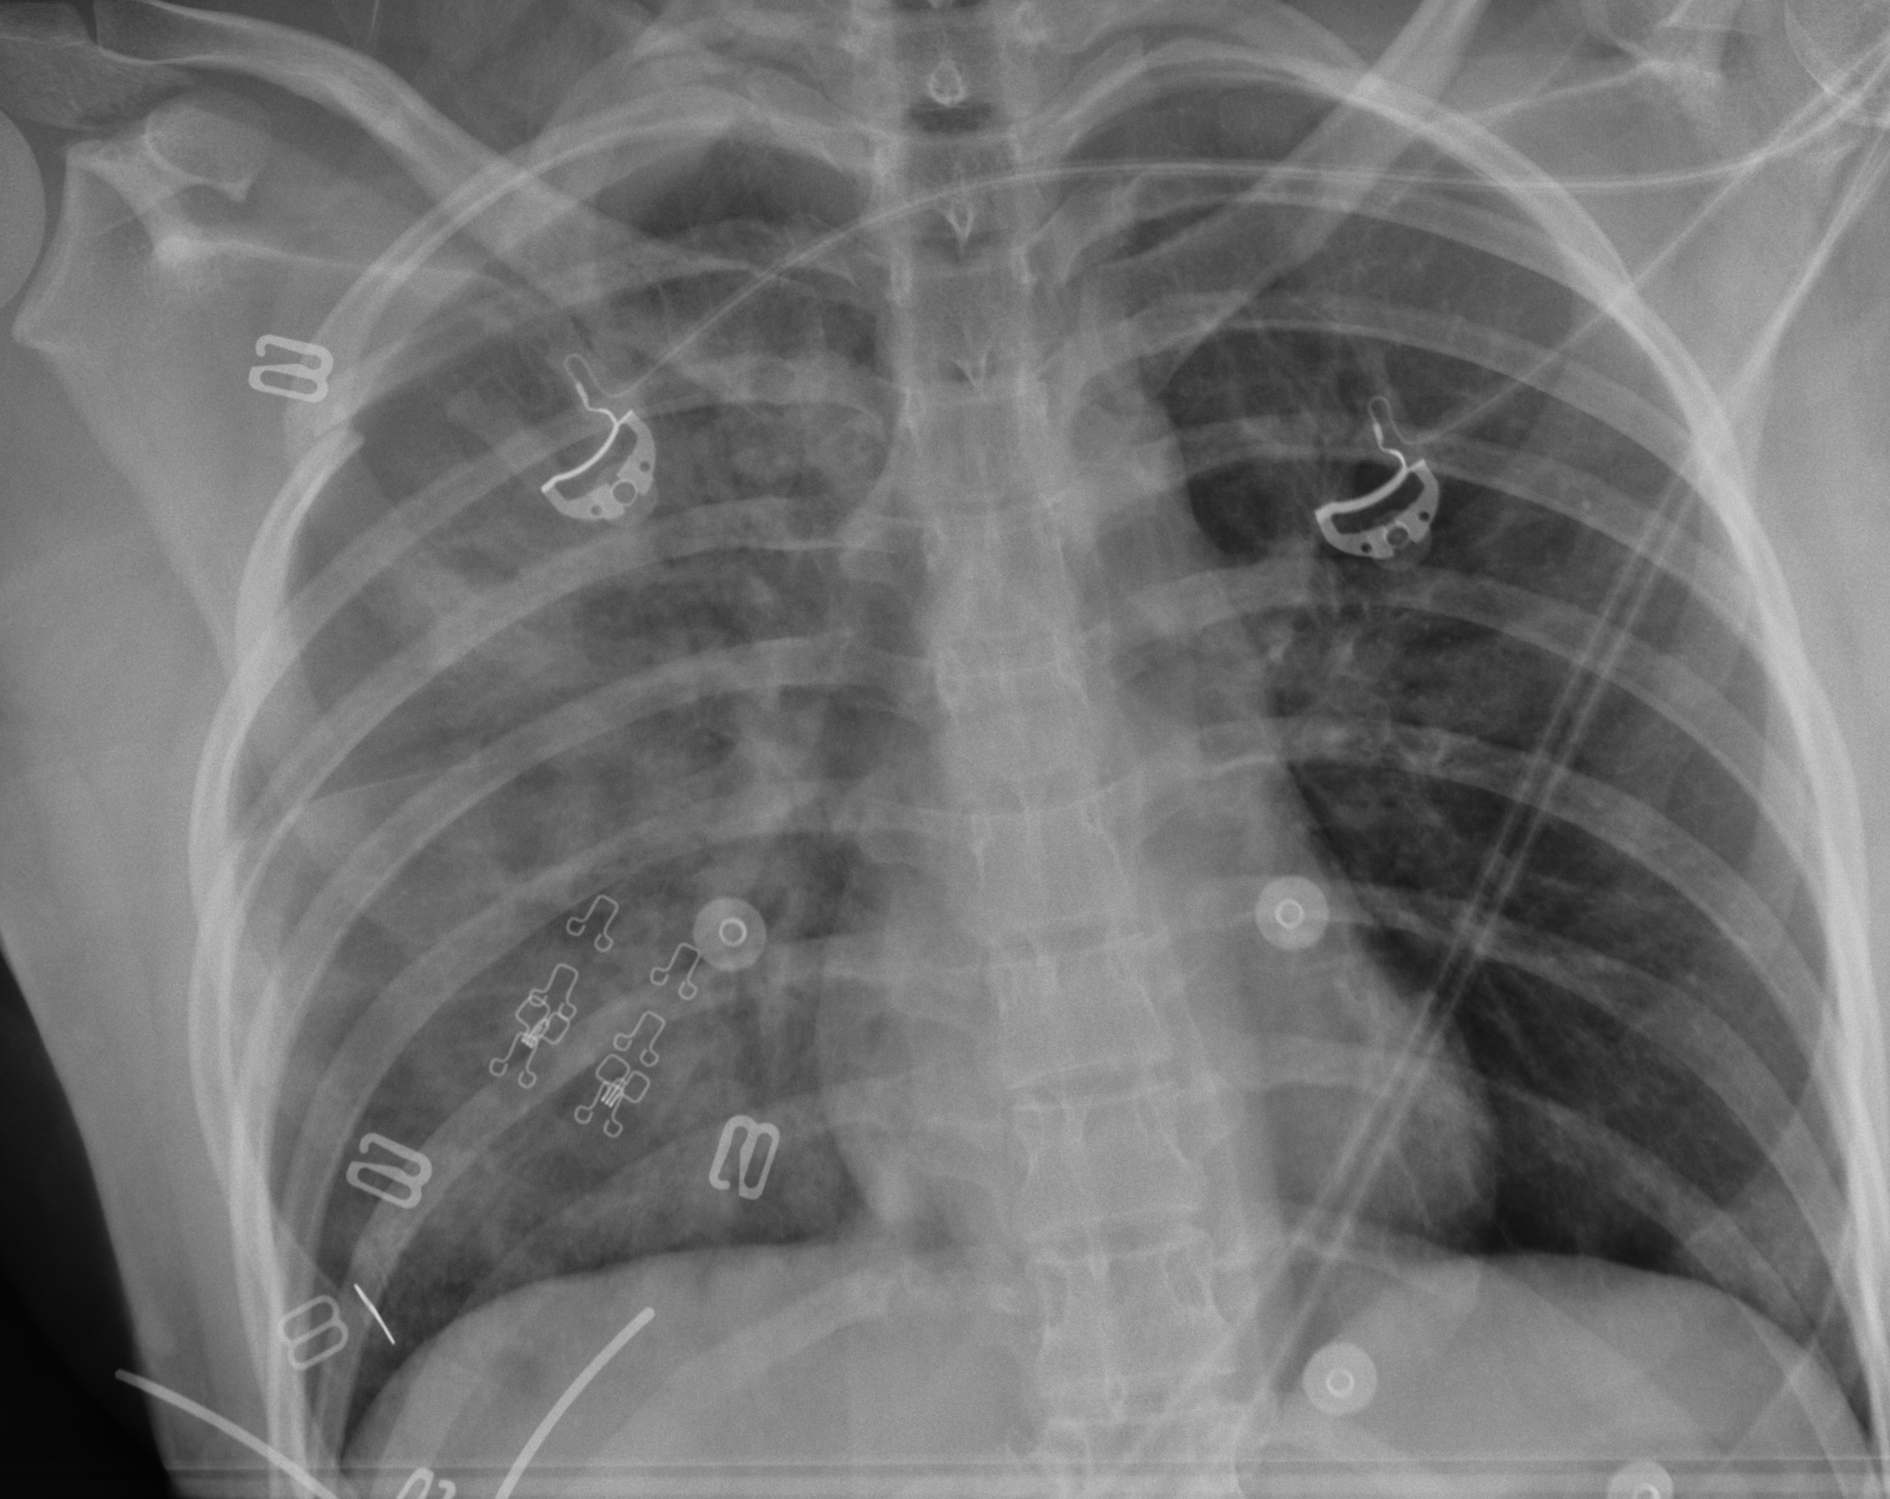

Pneumothorax / haemothorax

- decreased breath sounds

Tension pneumothorax

- heart apex and trachea displaced

- heart sounds (muffled + distended neck veins = cardiac tamponade)

Tension Pneumothorax / Needle thoracostomy

- second intercostal space in midclavicular line

- large gauge needle / 16G

- will hear hiss if tension

- need to place ICC

Pneumothorax / Hemothorax / Intercostal Catheter

- 5th intercostal space just anterior to midaxillary line

- need to avoid spleen / liver

- level with nipple

- use larger tube if for haemothorax

- CXR (hemothorax / widened mediastinum)